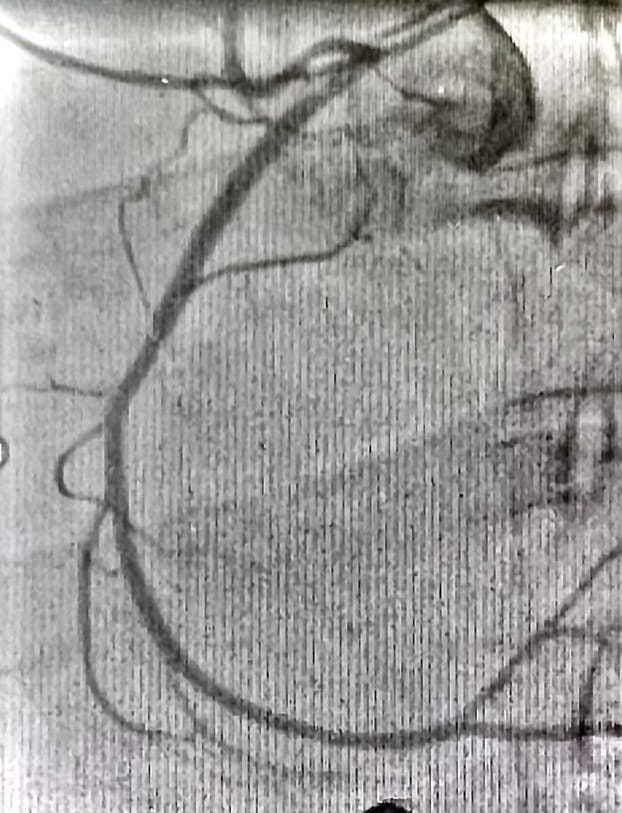

The above image shows the patient has anomalous origin of the right coronary artery which could not be visualized via femoral artery. Whenever the femoral approach is incomplete or unsuccessful, the radial approach is a critical alternative. In addition, radial arterial approach has been shown to reduce vascular complications compared to femoral arterial approach in a variety of clinical conditions.

He received a long stent to treat two lesions in the LAD at a local hospital, but the right coronary artery (RCA) could not be visualized despite two catheterizations via the femoral approach. After arriving at UPMC in cardiogenic shock, intubated state, the RCA was visualized and stented via radial approach using the 6 Fr left coronary AMPLATZ-1 guide by Krishna Tummalapalli, MD.